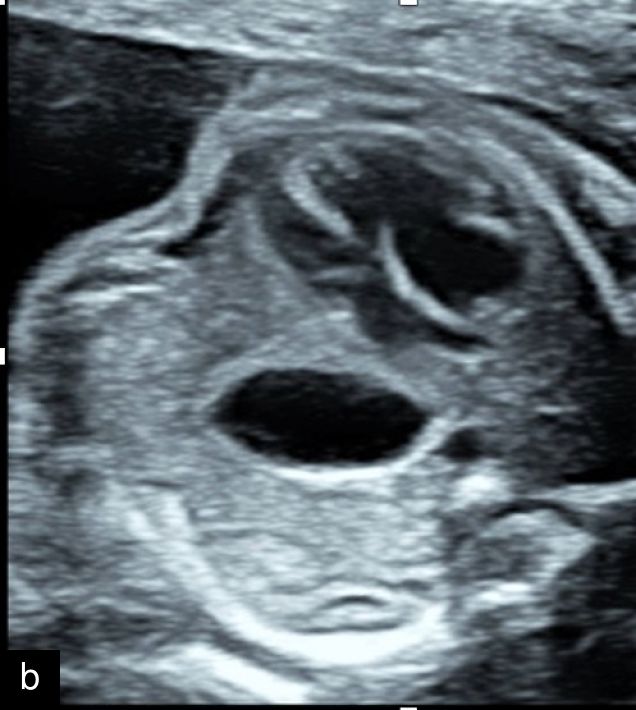

9

Micrognathia at 12 weeks on sagittal (a) and coronal (b) views and at 20 weeks on sagittal view (c).

Micrognathia can be determined subjectively but, more recently, diagnostic indices such as the inferior facial angle (comparing the frontal bone to a line drawn at the angle of the mentum), frontonasomental angle (comparing the frontal bone to a line drawn at the tip of the nose and mentum) and jaw index (comparing the axial mandibular diameter to the anteroposterior distance of the mandible) have been developed.23,24 Micrognathia may be less apparent with continued growth and development, particularly if diagnosed in the first or early second trimester, and therefore evaluation with these diagnostic indices may be particularly useful in these cases, along with careful follow-up.23